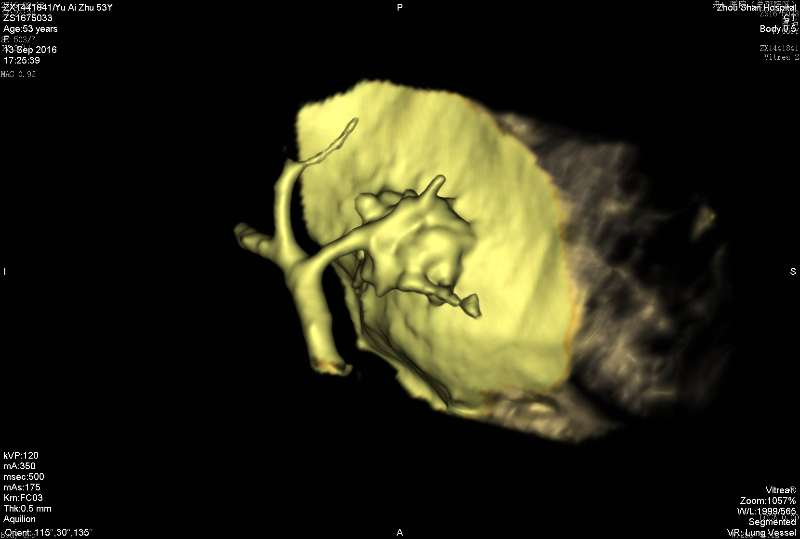

第三例曲霉菌:

3rd 在隔离肺的支气管里 也是在扩张的支气管内,有炎症细胞 紫红的可能是锰铁化,曲霉菌能吸收空气中的锰铁元素,在周边